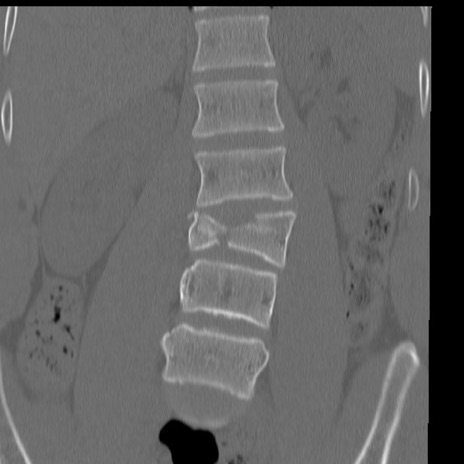

症例3 腰椎CT(冠状断像)

異常所見と診断は?

腰椎CT